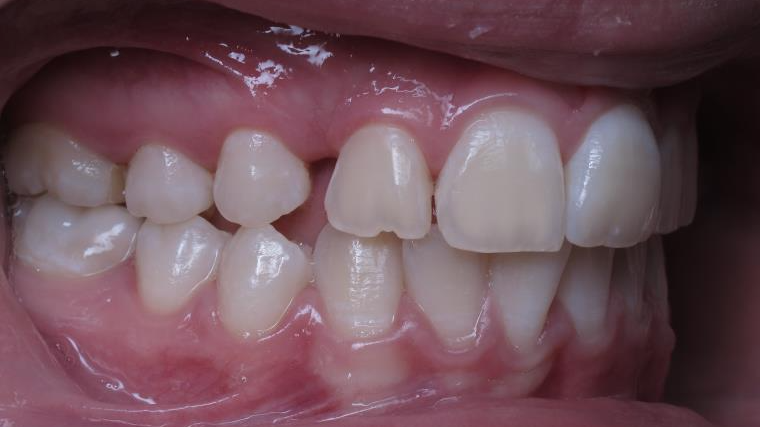

inversion des dents posterieur cote gauche

sectionnel multibagues pendant 25 mois

surveillance évolution de la dentition pendant 4 ans